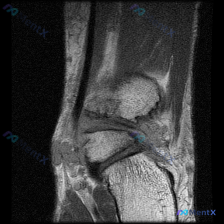

踝关节MRI读片病例分享,整理了完整分析思路 这是一例踝关节矢状位T2加权MRI,我把影像发现和分析思路整理出来,和大家一起讨论。 一、基本影像信息 这是踝关节MRI T2序列矢状位图像,可观察到胫骨远端、距骨、跟骨及周围软组织结构,核心阳性征象如下: 1. 骨骼关节改变:距骨穹窿(圆顶)可见明确局...

看到一份很有代表性的踝关节MRI影像,整理了资料和分析思路分享给大家。 病例影像基本信息 这是一份踝关节矢状位T2加权像(T2WI),先给大家说下客观观察到的结果: 1. 解剖结构显示清晰:可以看到胫骨远端、距骨、跟骨、足舟骨及部分跖骨 2. 核心异常发现: - 胫距关节腔前方、后方可见明显T2高信...

最近看到这例踝关节MRI读片讨论,问题是「图像中能观察到什么软组织液相关改变」,整理一下完整分析思路,分享给大家。 一、病例影像核心信息 这是踝关节MRI冠状位T2加权图像,核心发现如下: 1. 骨结构改变:胫骨远端、距骨、跟骨显影清晰,距骨穹窿内侧关节面可见局灶性高信号改变,边界清晰,呈楔形凹陷状...